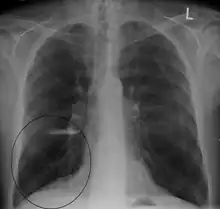

A chest X-ray and complete blood count may be useful to exclude other conditions at the time of diagnosis.[82] Characteristic signs on X-ray are hyperinflated lungs, a flattened diaphragm, increased retrosternal airspace, and bullae, while it can help exclude other lung diseases, such as pneumonia, pulmonary edema, or a pneumothorax.[83] A high-resolution CT scan of the chest may show the distribution of emphysema throughout the lungs and can also be useful to exclude other lung diseases.[25] Unless surgery is planned, however, this rarely affects management.[25] A saber-sheath trachea deformity may also be present.[84] An analysis of arterial blood is used to determine the need for oxygen; this is recommended in those with an FEV1 less than 35% predicted, those with a peripheral oxygen saturation less than 92%, and those with symptoms of congestive heart failure.[24] In areas of the world where alpha-1 antitrypsin deficiency is common, people with COPD (particularly those below the age of 45 and with emphysema affecting the lower parts of the lungs) should be considered for testing.[24]

A lateral chest X-ray of a person with emphysema: Note the barrel chest and flat diaphragm.

Lung bulla as seen on chest X-ray in a person with severe COPD